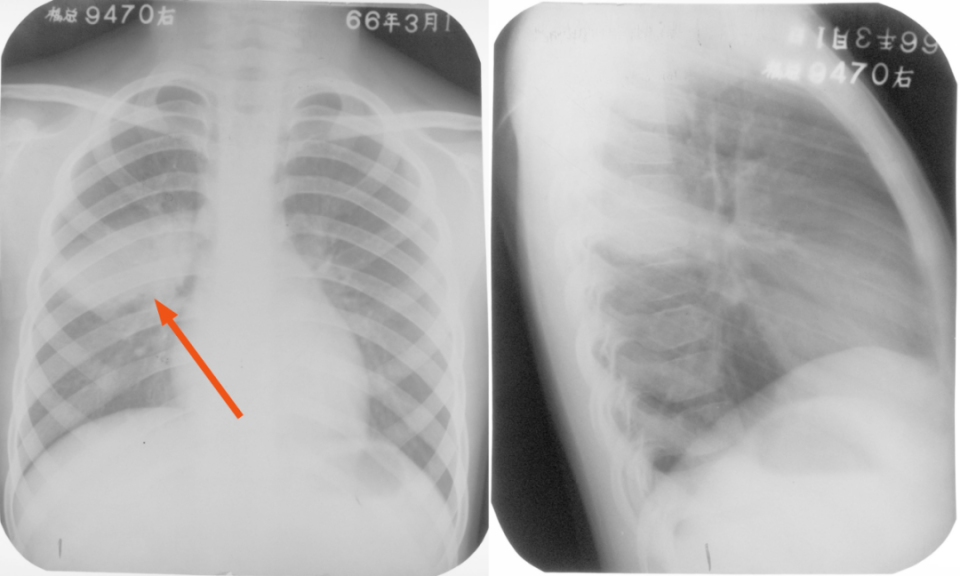

胸部正侧位片

图片

胸部右侧位片